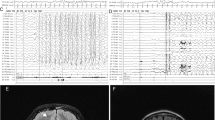

The ubiquitin–proteasome system is the principal system for protein degradation mediated by ubiquitination and is involved in various cellular processes. Cullin-RING ligases (CRL) are one class of E3 ubiquitin ligases that mediate polyubiquitination of specific target proteins, leading to decomposition of the substrate. Cullin 3 (CUL3) is a member of the Cullin family proteins, which act as scaffolds of CRL. Here we describe three cases of global developmental delays, with or without epilepsy, who had de novo CUL3 variants. One missense variant c.854T>C, p.(Val285Ala) and two frameshift variants c.137delG, p.(Arg46Leufs*32) and c.1239del, p.(Asp413Glufs*42) were identified by whole-exome sequencing. The Val285 residue located in the Cullin N-terminal domain and p.Val285Ala CUL3 mutant showed significantly weaker interactions to the BTB domain proteins than wild-type CUL3. Our findings suggest that de novo CUL3 variants may cause structural instability of the CRL complex and impairment of the ubiquitin–proteasome system, leading to diverse neuropsychiatric disorders.

Nakashima, M., Kato, M., Matsukura, M. et al. De novo variants in CUL3 are associated with global developmental delays with or without infantile spasms. J Hum Genet 65, 727–734 (2020). https://doi.org/10.1038/s10038-020-0758-2